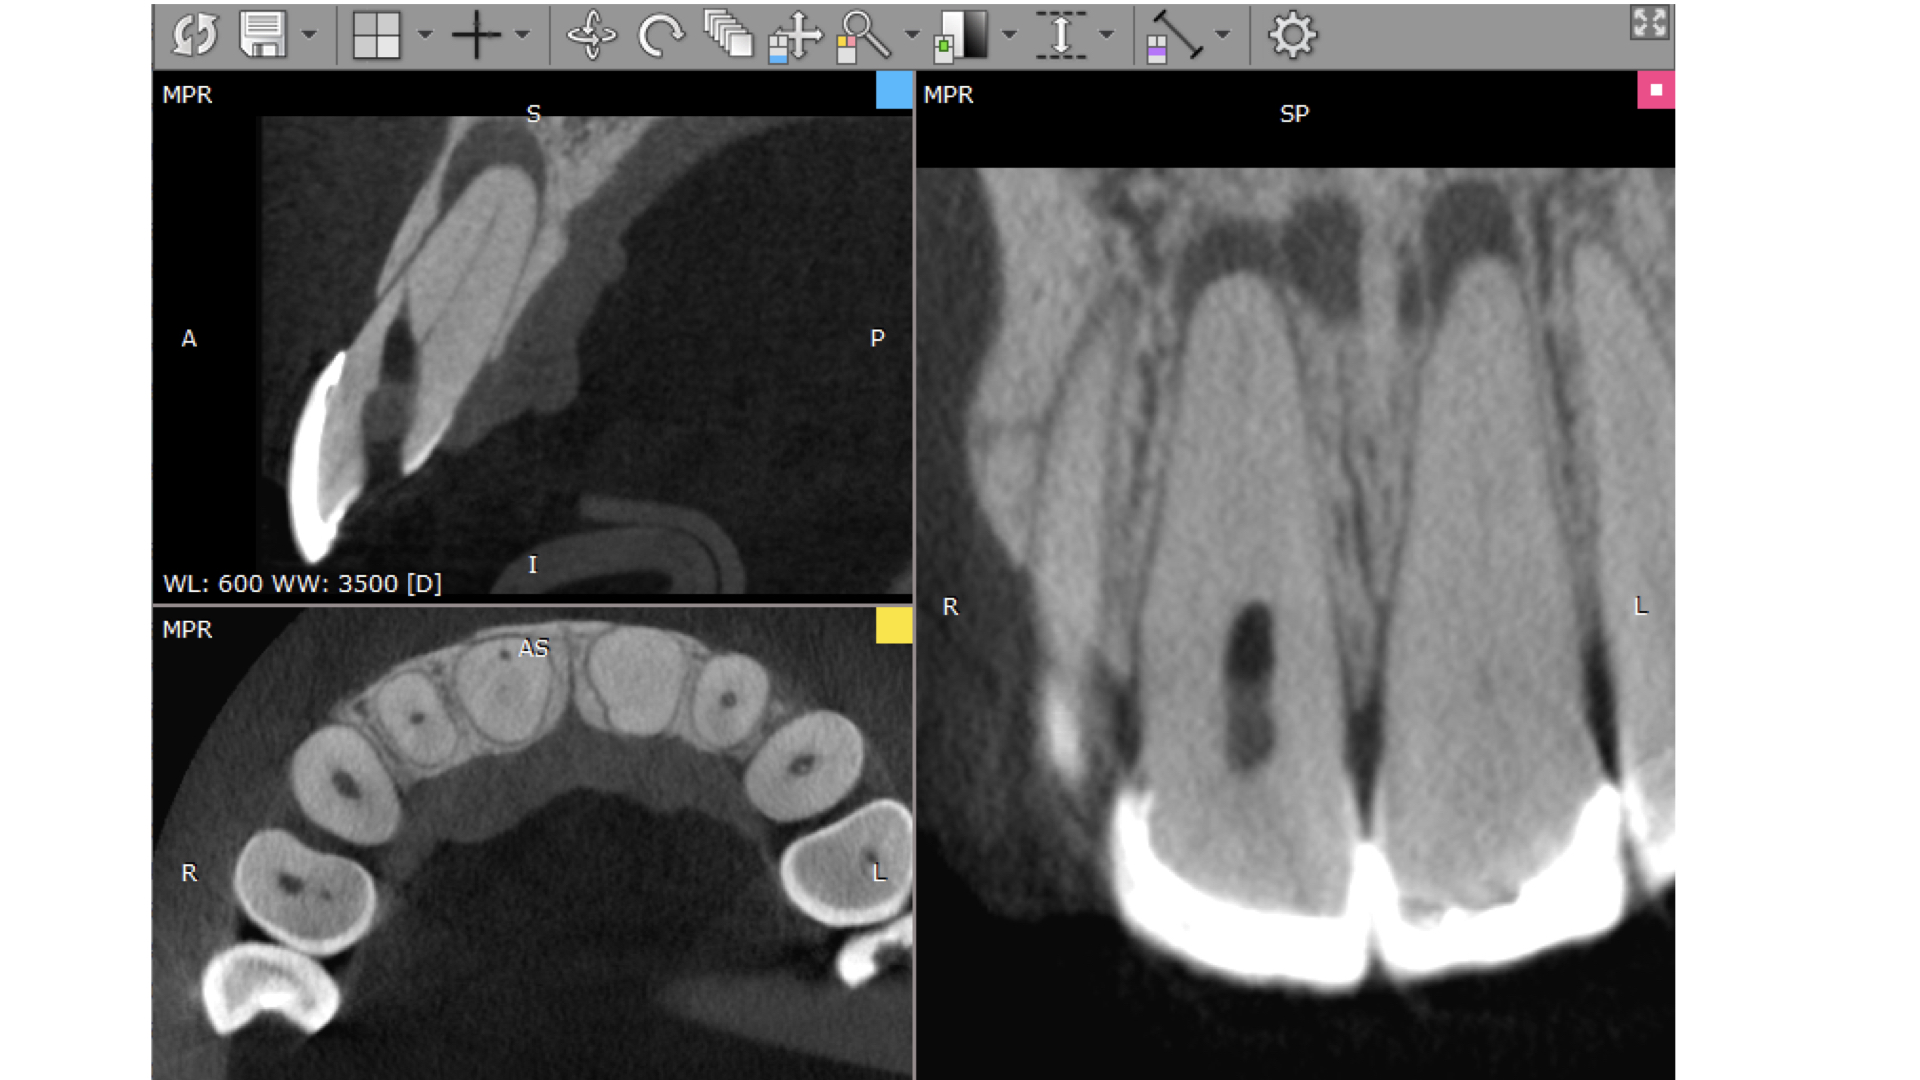

- Solicitação de uma tomografia computadorizada da arcada em que será feito o endoguide (figura 1).